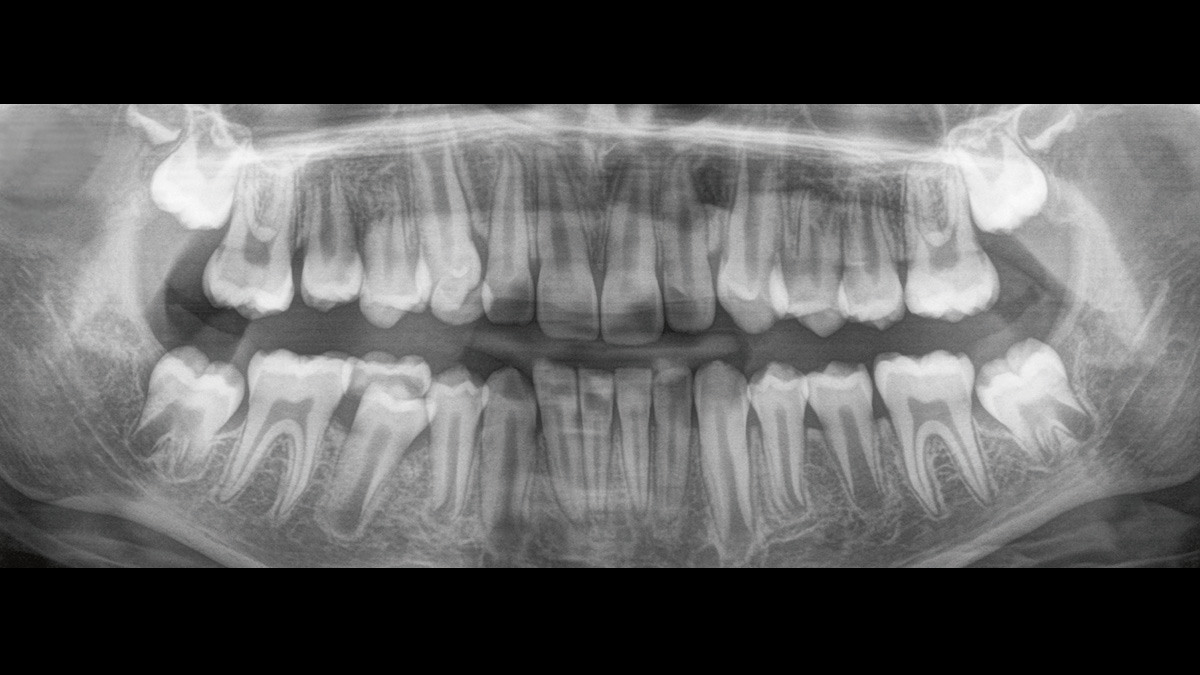

Der 2D/3D Power Performer Orthophos SL ist eine großartige Wahl für alle, die einfach mehr wollen. Der integrierte Direct Conversion Sensor (DCS) wurde für anspruchsvolle Bildqualitätsstandards entwickelt und bietet detaillierte Daten. Der intelligente Autofokus liefert automatisch fokussierte Panoramabilder mit hervorragender Gesamtschärfe. Orthophos SL bietet höchsten Bedienkomfort durch automatische Positionierung, eine anwenderfreundliche, intuitive Bedienung mit dem EasyPad und ein individuell einstellbares Umgebungslicht für ein exklusives Erscheinungsbild.

Der Direct Conversion Sensor erfüllt besonders hohe Standards für die 2D-Bildgebung

Der Autofokus erzeugt aus mehreren tausend Einzelbildern automatisch eine beeindruckende scharfe Panorama-Röntgenaufnahme

Mit dem Low Dose-Modus erhalten Sie 3D-Bilder im Dosisbereich einer 2D-Röntgenaufnahme. Im HD-Modus werden während eines einzelnen Umlaufs mehr als 800 Einzelbilder aufgenommen und zu einem 3D-Volumen mit bis zu 80 μm zusammengeführt. Der Vorteil für Sie: rauschärmere Aufnahmen in hoher Auflösung

Der Direct Conversion Sensor (DCS) hat den Standard der Panorama-Bildgebung neu definiert. Röntgenstrahlen werden direkt in elektrische Signale umgewandelt – im Gegensatz zu herkömmlichen Systemen gibt es keinen Signalverlust durch Lichtumwandlung, was eine verbesserte Bildgebung ermöglicht. Das Ergebnis sind Bilder mit einer sehr hohen Schärfe, selbst bei niedriger Dosis.

Eine Röntgenaufnahme muss sofort diagnostizierbar sein. Der Autofokus hilft dabei erheblich. Orthophos SL erfasst mehrere tausend Einzelbilder in einem Zyklus und erkennt automatisch scharfe Bereiche, um ein gleichmäßig scharfes Gesamtbild zu erzeugen. Der intelligente Autofokus erfordert keine manuellen Arbeitsschritte vor und nach der Erfassung.